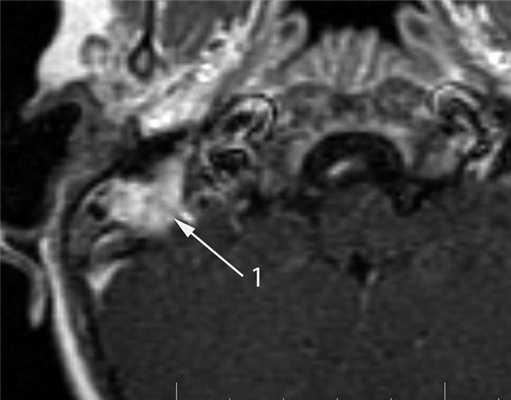

КТ-признаки злокачественной опухоли височной кости предопределяются происходящими в ней патоморфологическими изменениями. Так, наличие опухолевых масс в среднем ухе на КТ проявляется нарушением пневматизации полостей среднего уха (рис. 1). Рисунок 1. Лангергансоклеточный гистиоцитоз. Аксиальная проекция правой височной кости. Отсутствует пневматизация полостей среднего уха за счет наличия опухоли (1), вызывающей обширные деструктивные изменения в пирамиде. Цепь слуховых косточек сохранена (2). Степень выраженности данного КТ-симптома обусловлена размерами самой опухоли и ее точной локализацией в височной кости. Нарушение пневматизации полостей среднего уха не является специфичным для новообразований и постоянно встречается при других заболеваниях среднего уха, в первую очередь при остром и хроническом средних отитах.